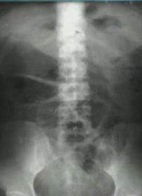

1.X線檢查

(1)腹部平片 ①胃、小腸和結腸有充氣呈輕度至重度擴張。小腸充氣可輕可重,結腸充氣多數較顯著,常表現為腹周全結腸框充氣。②腹部立位平片:擴張的胃和小腸、結腸內出現寬窄不一的液平面。③結腸糞便不論是顆粒糊狀或是糞便塊狀糞團,是確認結腸的可靠徵象。④急性腹膜炎者常於腹平片中出現腹腔積液征,嚴重者還可出現腹脂線模糊。⑤腸壁因水腫、充血而增厚甚至出現橫膈動作受限,肋膈角變鈍等胸腔積液徵象。

根據病人病史、臨床表現,結合X線、CT等檢查診斷即可明確。立位X線平片檢查時,往往全部腸襻有充氣擴張現象,並可見腸腔內有多個液平面。但也有少數病例只有個別腸襻發生局限性的腸麻痹。

本病宜與機械性腸梗阻相鑑別。後者常與腸腔堵塞、小腸先天性畸形和腸外壓迫等疾病有關,臨床表現以陣發性腹絞痛為主要表現,聽診腸鳴音亢進;而麻痹性腸梗阻多為持續性脹痛,無絞痛發作,腸鳴音減弱或消失。X線檢查,機械性腸梗阻時充氣腸襯大小不一;麻痹性腸梗阻則可見胃腸道普通脹氣,小腸充氣腸襻大小較為一致。